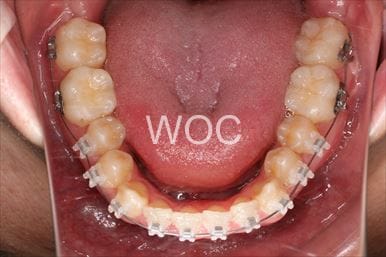

治療中1

治療中2

治療中3

治療中4

治療中5